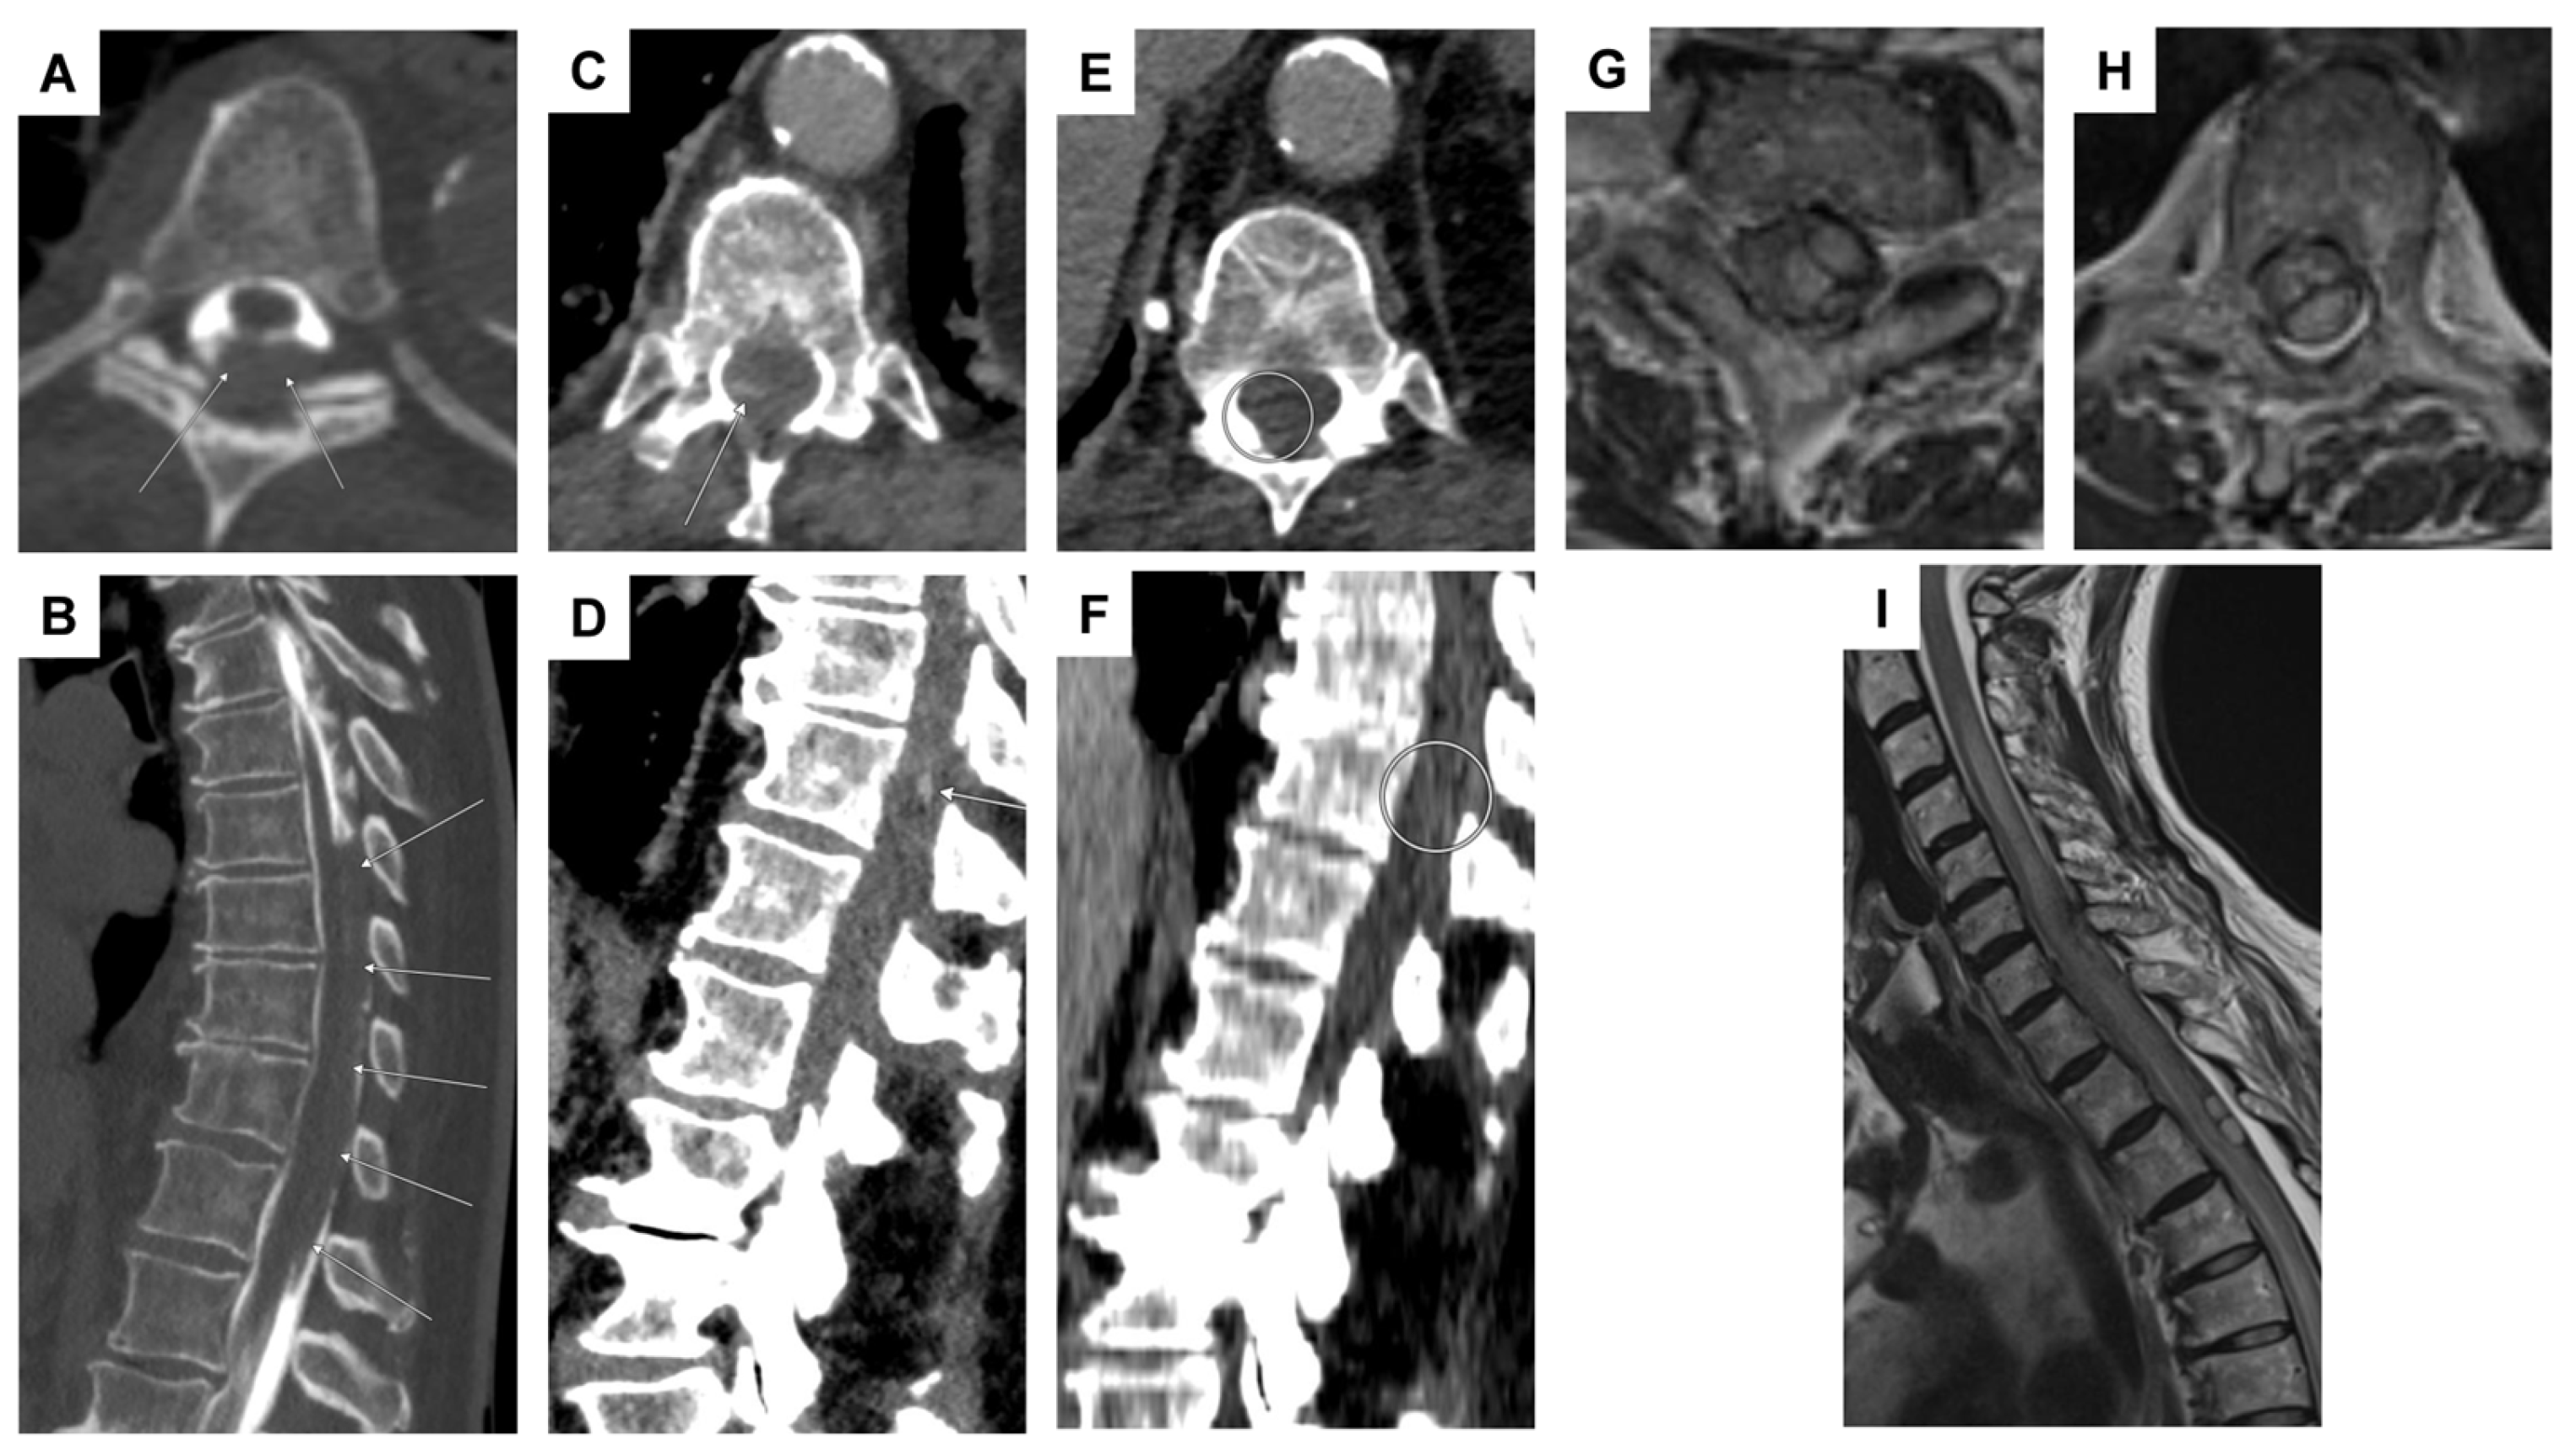

| 1 | F | 47 | headaches and pain in the back/neck pain, nausea, vomiting, photophobia/phonophobia | no focal neurological deficit | SAH Fisher IV with spinal aneurysm at T1 | aneurysm | lumbar puncture, multiple DSA, multiple spinal MRI | conservative |

| 2 | F | 69 | headaches and abdominal complaints | oriented 3×, marked meningism, positive Lasègue sign | spinal SAH with (partial) thrombosed intraspinal aneurysm at T2 | aneurysm | multiple DSA, multiple spinal MRI | surgical procedure (resection of the aneurysm) |

| 4 | F | 86 | iliosacral pain, paraparesis of the legs, and hypoesthesia from T11 | no evidence of manifest paralysis, intact sensation, unavailable reflexes in the lower extremities | spinal SAH; initially suspected T11 aneurysm; angiographically, no evidence of an aneurysm (spot sign) | anticoagulation (apixaban) | 2 lumbar punctures, repeated abdominal/thoracic CTA, DSA | conservative |

| 5 | F | 73 | headaches and pain in the back/neck pain | pronounced paraparesis of both legs | spinal SAH; angiographically, no evidence of an aneurysm | anticoagulation (rivaroxaban) | abdominal/thoracic CTA, multiple DSA, multiple spinal MRI | surgical procedure (evacuation of an intradural hematoma) |

| 6 | M | 55 | pain between the shoulder blades and the cervical spine, tingling sensations in all four extremities | tingling sensations in all extremities, unable to lift the legs, weakness in both arms | epidural bleeding and spinal SAH; suspected perimedullary aneurysm at T1/2; angiographically, no evidence of an aneurysm, epidural bleeding may be due to a microspur at T1/2 | microspur | multiple DSA, multiple spinal MRI | surgical procedure (evacuation of an epidural hematoma), then conservative (no evidence of an aneurysm) |